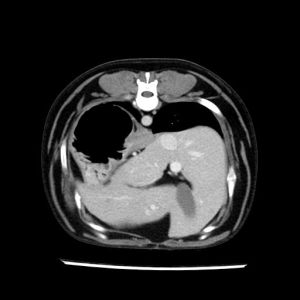

La lesione focale epatica , la ceus,la Tac e il chirurgo .